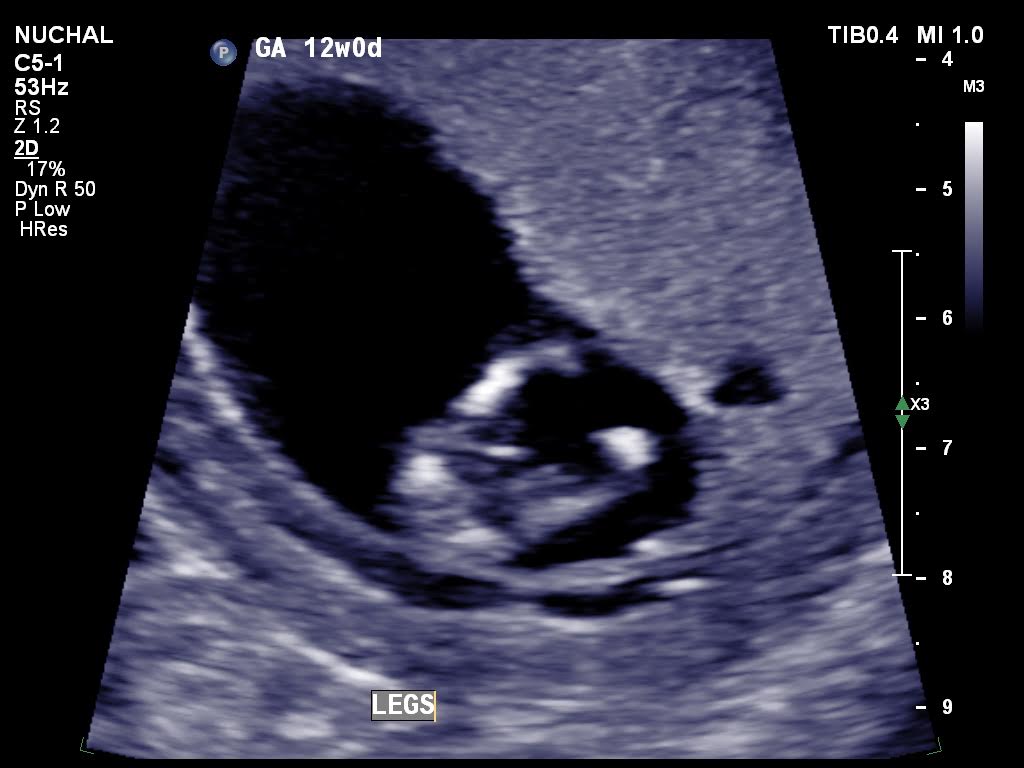

Is it possible for anybody to suggest the gender please from these 12 weeks ultrasound scans.